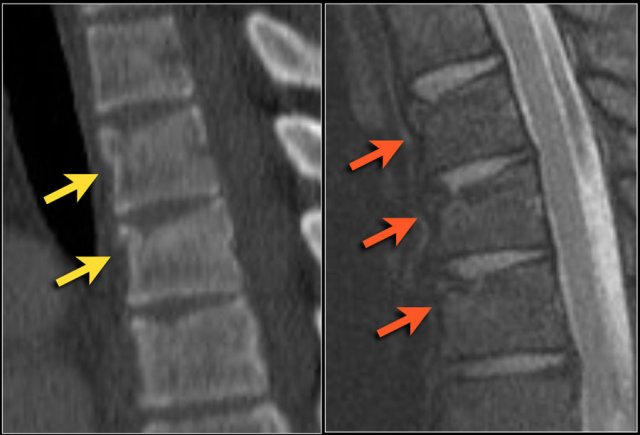

In this case the main findings are the horizontal fractures of the posterior elements.

The vertebral body fractures show hardly any compression.

Notice that there are 3 vertebrae involved.

Only the level with the highest score counts.

TLICS score based on imaging is 7 points:

• Distraction: 4 points

• PLC involvement: 3 points

The findings are:

1. The main feature is posterior distraction with horizontal fractures of posterior elements (red arrow)

2. Avulsion of a spinous process (yellow arrow)

3. Widening of facet joint (green arrow)

4. Burst-type fracture

In this case some would call this a burst fracture with PLC-injury i.e. 2+3 points.

However the distraction is the most important finding, i.e. distraction and PLC injury, i.e. 4+3 points.